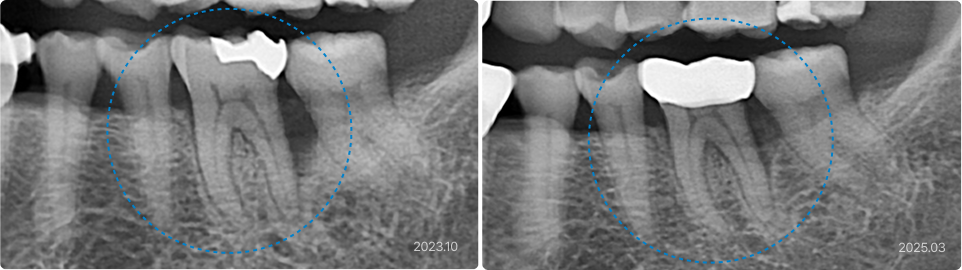

02

약해진 잇몸과 뼈, 잇몸 재생 치료로 지켜낸 편안한 일상

치료 전

치료 후

치료 내용

• 이전에 치료받은 치아의 잇몸이 내려가서 빈공간에 잦은 염증

• 치주수술 + 엠도게인 적용으로 잇몸 재생 유도

• 치료 후 잇몸과 잇몸 뼈가 재생되어 빈 공간이 채워짐

초기 염증, 출혈은 몇 주에서 수개월에 걸쳐 차분히 호전됩니다.

잇몸 주머니 깊이와 붙는 힘 등 임상 지표 변화는 보통 3~6개월 후 확인할 수 있으며,

X-ray에서 뼈 무늬 변화는 대게 6~12개월 이후 평가합니다. 참고로 엠도게인 재료 자체는 X-ray에 보이지 않습니다.